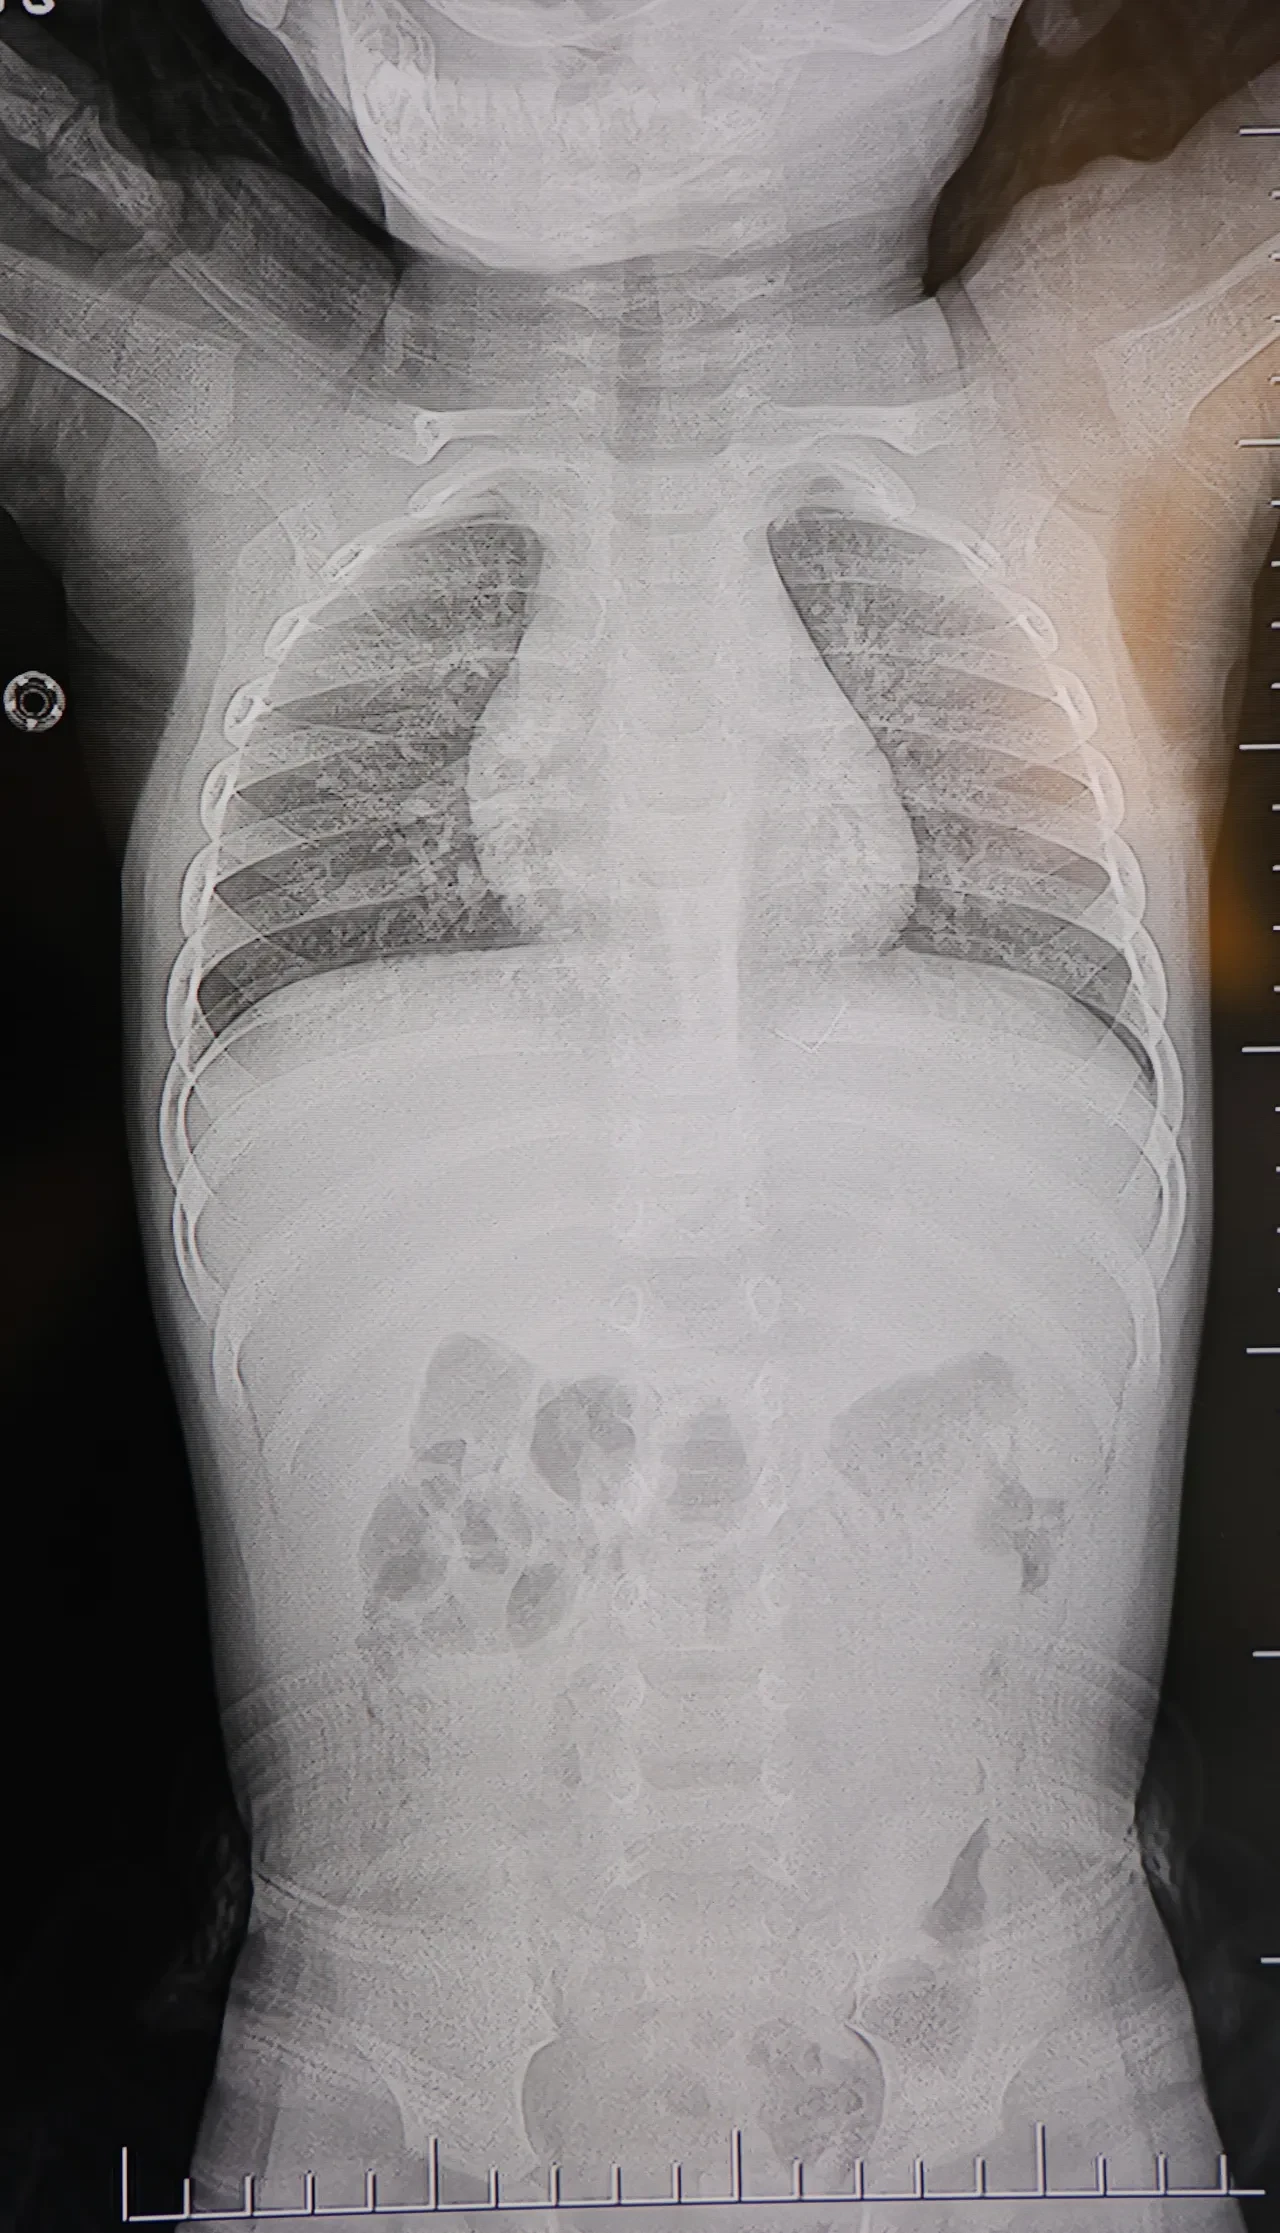

Ailenin bebekleri için son başvurduğu hastanede Beyin ve Sinir Cerrahisi Uzmanı Prof. Dr. İdris Altun tarafından yapılan tetkiklerde, yabancı cismin cilt altında, omurilik kanalına yakın bir bölgede olduğu ve akciğer zarına doğru ilerlediği belirlendi.

Talihsiz bebek, genel anesteziye alınmadan, lokal anestezi ve sedasyon eşliğinde ameliyata alındı. Yapılan müdahalede yabancı cisim tamamen çıkarıldı. Çıkarılan cismin, ince zımba teline benzer metal bir tel olduğu ve yaklaşık 2 santimetre uzunluğunda bulunduğu tespit edildi. Hasta, aynı gün taburcu edildi.

Konuya ilişkin açıklama yapan Prof. Dr. İdris Altun, "Sırtında yabancı bir cisim olduğu söylenmiş ancak çıkarılamayacağı ve 8 yaşına kadar beklenmesi gerektiği ifade edilmişti. Bize başvurduğunda yaptığımız tetkiklerde, cilt altında, omurilik kanalına çok yakın ve akciğer zarına doğru ilerleyen bir yabancı cisim tespit ettik. Hastamızı tamamen uyutmadan, lokal anestezi ve sedasyon eşliğinde müdahale ederek lezyonu tamamen çıkardık. Çıkardığımız cismin ince zımba teline benzer, yaklaşık 2 santimetre uzunluğunda metal bir tel olduğunu gördük. Bu yabancı cisim alınmasaydı, bölgede enfeksiyon gelişebilirdi. Enfeksiyon sonucu omurilik kanalında ciddi hasarlar oluşabilir, çocuk büyüdükçe cismin hareket etmesine bağlı olarak omurilikte zedelenmeler meydana gelebilirdi. Ayrıca yana doğru ilerleyerek akciğer zarına ve akciğere batma riski vardı. Bu da enfeksiyona ve ilerleyen süreçte tümörle karışabilecek tablolara neden olabilirdi. Şu an hastamız gayet sağlıklı. Gerekli kontrolleri yaptık ve aynı gün taburcu ettik" dedi.